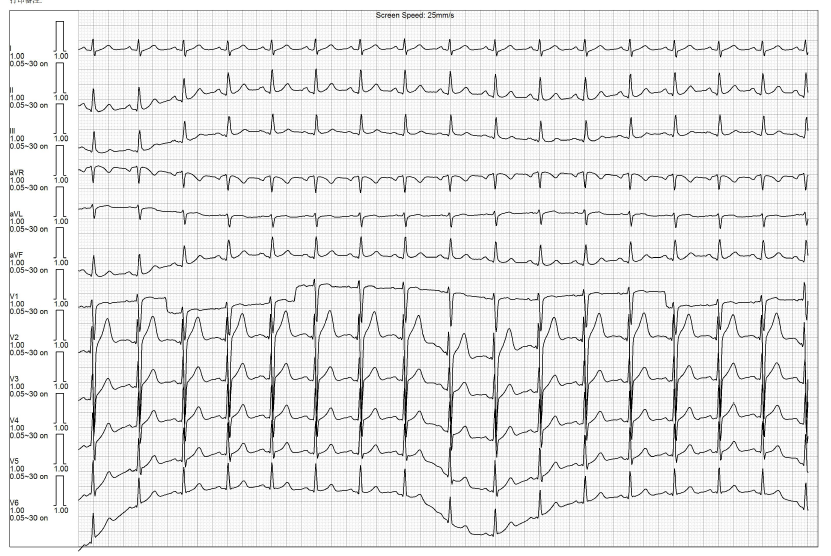

男性,72岁,因“反复心悸1年余”入院,有浸润性肺结核病史,目前服用抗结核药物;Holter显示室早18461个,占比17.23%;入院体表心电图示三联律。

图片

术前Holter心电图

穿刺置入导管后使用Columbus®系统在右室建模行激动标测,在流出道瓣上标记到提前体表30ms,单极QS型,消融放电后室早仍存在,但I导联形态发生改变,进行巩固消融无效。应用Columbus®系统对流出道瓣下进行激动标测,标记提前体表32ms,单极QS型,后放电消融无效。随后,穿刺股动脉在左室建模进行激动标测未找到提前体表的靶点。重新对右室建模进行激动标测,在低位间隔处标记提前体表40ms最早点,单极QS型,再次放电消融后早搏消失,继续消融120s后观察两到三分钟,室早复现。对靶点附件巩固消融发现消融时室早消失,停止消融时室早又复现,为了安全起见,没有继续巩固。术后复查动态心电图显示室早数量明显减少,患者自觉症状好转。

应用Columbus®系统在右室标测低位间隔处,标记提前体表40ms最早点

术后心电图